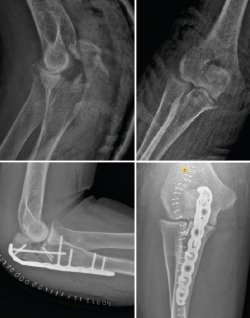

Fractura-luxación transolecraneana

Esta lesión se encuentra dentro del espectro de las lesiones de la inestabilidad compleja de codo, aunque existen diferentes estudios donde se ha reportado la ausencia de lesión discernible en los estabilizadores ligamentosos(34,35,36). Esto comporta que el principio fundamental del tratamiento de estas lesiones es restablecer la anatomía de la fosa sigmoidea mayor y la coronoides. Restablecer la estabilidad del principal estabilizador del codo (articulación ulnohumeral) es suficiente para restablecer la estabilidad del codo (Figura 16).

Figura 16. Fractura luxación transolecraneana de codo tratada quirúrgicamente mediante la reducción abierta anatómica y fijación interna con placa preconformada de cúbito proximal.

Las placas preconformadas de cúbito proximal son de elección en este tipo de fractura(37,38,39,40). Esto es debido a que nos permiten realizar una reducción anatómica de todos los fragmentos y restablecer tanto la anatomía de la fosa sigmoidea mayor como de la coronoides. En ocasiones, puede ser necesario el uso de injerto óseo para la reconstrucción de la fosa sigmoidea mayor, dado que estas fracturas suelen ser consecuencia de impactos de alta energía y puede encontrarse mucha conminución del foco de fractura(41). Los errores más comunes durante el manejo quirúrgico de estas fracturas-luxaciones son(42):